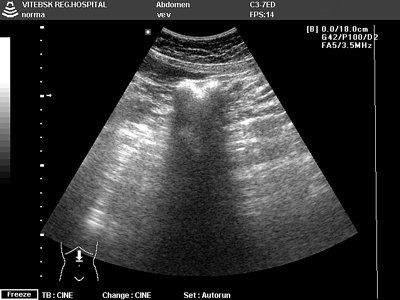

Опухоль кишечника на узи

Опухоль кишечника на узи 115 фото